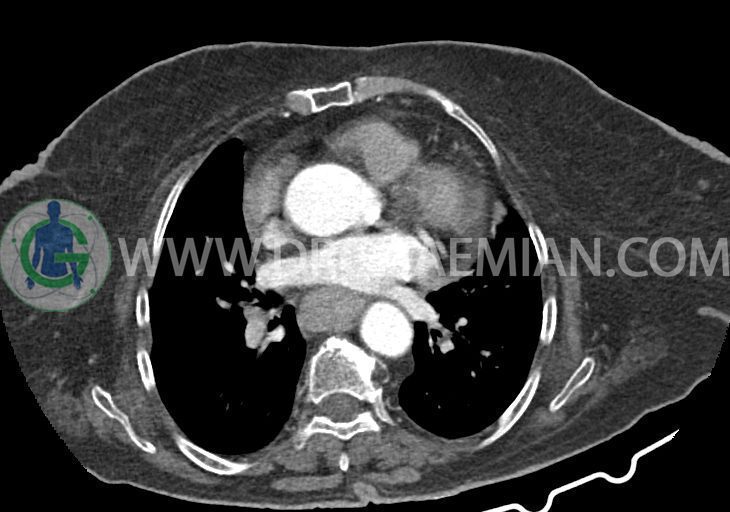

در سی تی اسکن اسپیرال ریه و مدیاستن – شکم و لگن با و بدون کنتراست خوراکی و وریدی (مولتی دیدکتور 16 با مقاطع ظریف و بازسازی های ساژیتال و کرونال):

–کاردیومگالی همراه با pericardial effusion خفیف

–یک ندول به ابعاد 19x18mm با حدود اسپیلوکه در سگمان لترال RML و دو ندول کوچکتر در مجاورت فوقانی آن به اقطار 6mm و 5mm ( مطرح کننده کارسینوم برونکوژنیک یا متاستاز )

–دیلاتاسیون نیمه فوقانی مری توراسیک ناشی از افزایش ضخامت circumferential توده مانند در یک سوم دیستال مری به طول 50mm ، که می تواند مطرح کننده انفیلتراسیون تومورال همراه با تنگی

–لنف نودهای non significant مدیاستینال با حداکثر SAD=6mm در فضای پره کارینا

–آئورت صعودی دیلاته به قطر 38mm